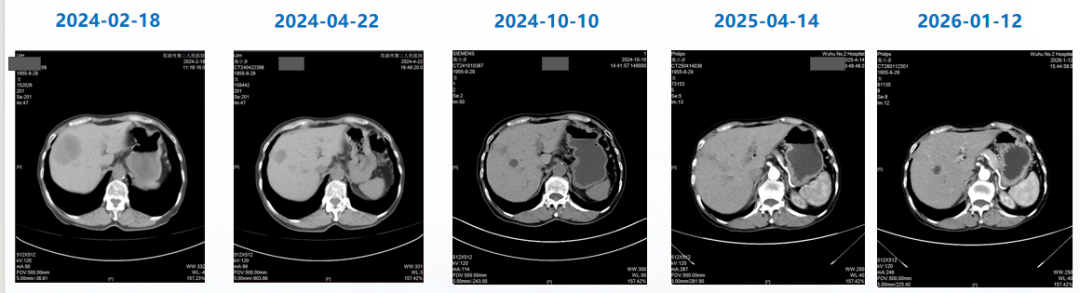

治疗3个周期后(2024-04-22),患者复查CT,肺转移灶、肝转移灶疗效评估达PR,至末次复查(2026-01-12)时评价为疾病稳定(SD),目前患者仍在继续T-DXd治疗;治疗期间未出现间质性肺病(ILD)/肺炎相关症状,甲状腺减退症状经对症处理后较前好转(促甲状腺素:4.695 mIU/L)

△患者肝转移灶影像变化